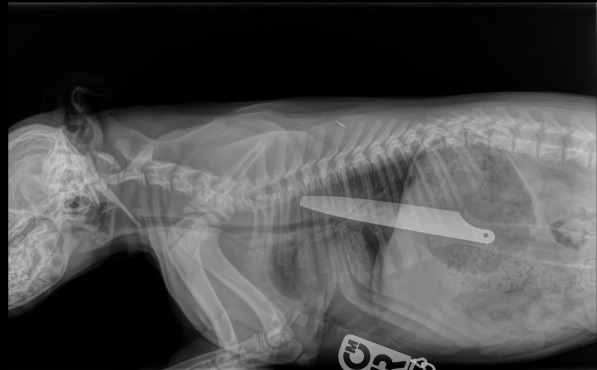

Gambar X-ray memperlihatkan pisau itu tersangkut di dalam tubuh Macie, anjing staffordshire bull terrier berusia 12 pekan.

Pegangan pisau itu melewati perut Macie dan ususnya, sementara ujung pisau masih di tenggorokannya.

Dokter hewan Emily Ronald mengatakan dia belum pernah melihat hasil x-ray seperti Macie sebelumnya.